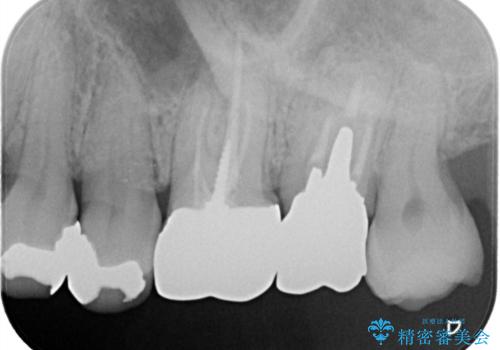

過去に装着されたメタルインレーを除去したのち、内部の虫歯を除去、セラミックインレーにて修復治療を行なっております。

e-maxプレスインレーを用いることで、高い精度と強度を達成することができました。